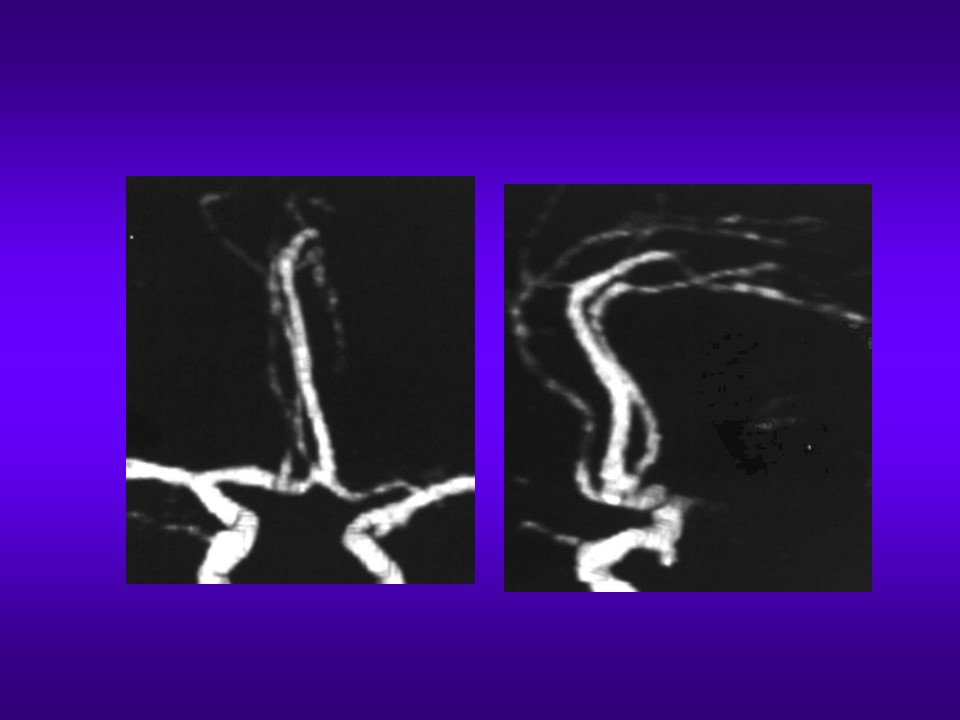

“头颈部CE-MRA正常表现与变异” 的相关文章